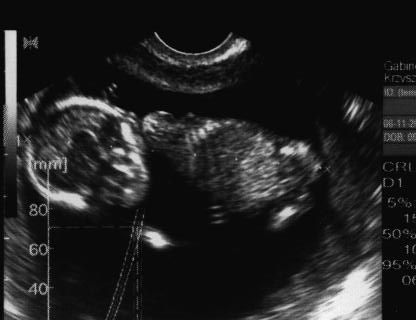

Właśnie wróciłam od lekarza, jest wszystko OK. Dzidzia zdrowa, oglądałam ją z każdej strony, spała z nogami po turecku

nawet rączkę miała troszkę w górze, mały akrobata rośnie.

Według USG to 12 tydzień i 1 dzień.

Lekarz zrobił przeziernośc karku i też jest wszystko OK. Jednak dzidzię podsłucham dopiero później, może za miesiąc, mówił że na wszystko będzie czas, troszkę chyba się śpieszył.